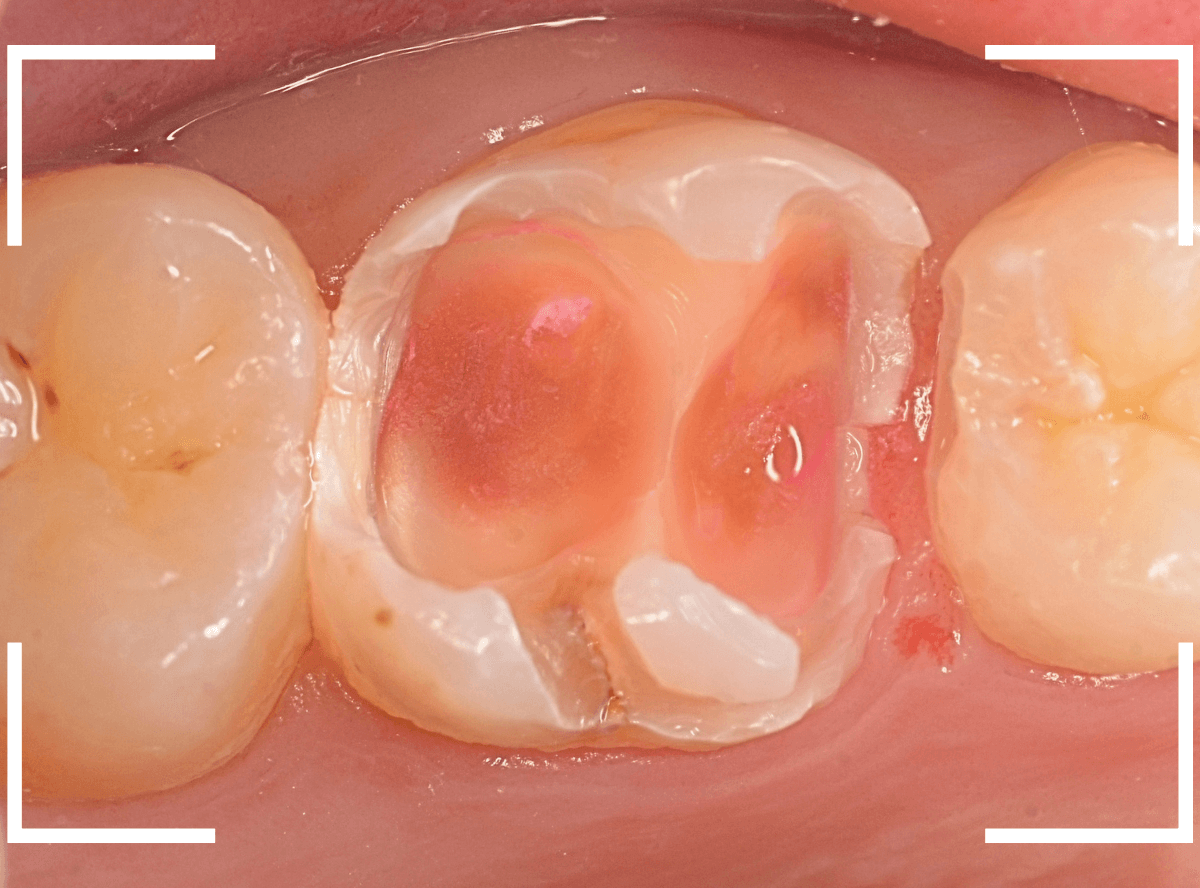

全ての虫歯を除去したところです。

抜歯した後ろのおやしらずは、元々虫歯の治療がしてありましたが、その際に抜歯しておいた方が良かったのではないかな、と思いました。